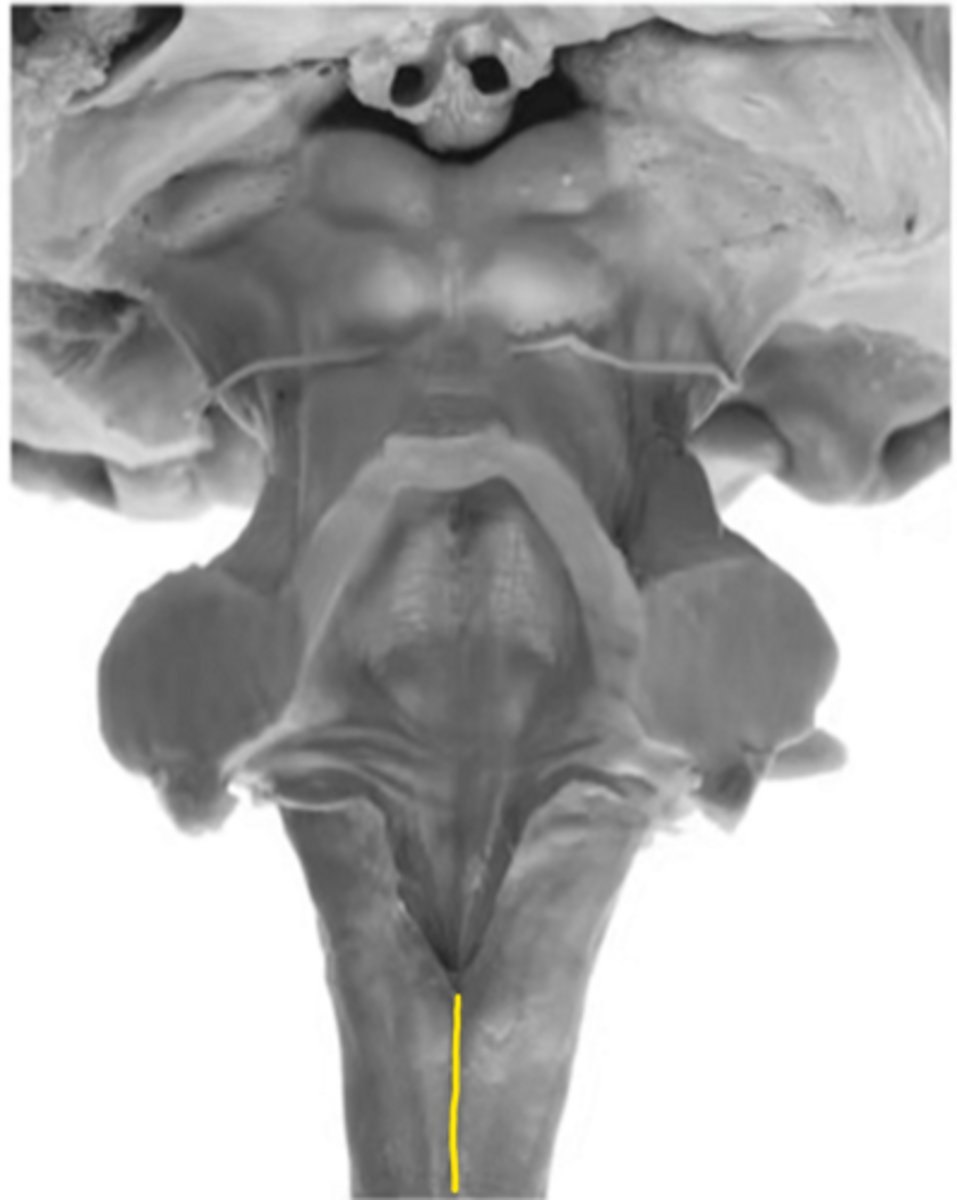

anterior median sulcus

ID the structure

motor decussation

central gray

central canal

closed medulla

ID the brainstem level